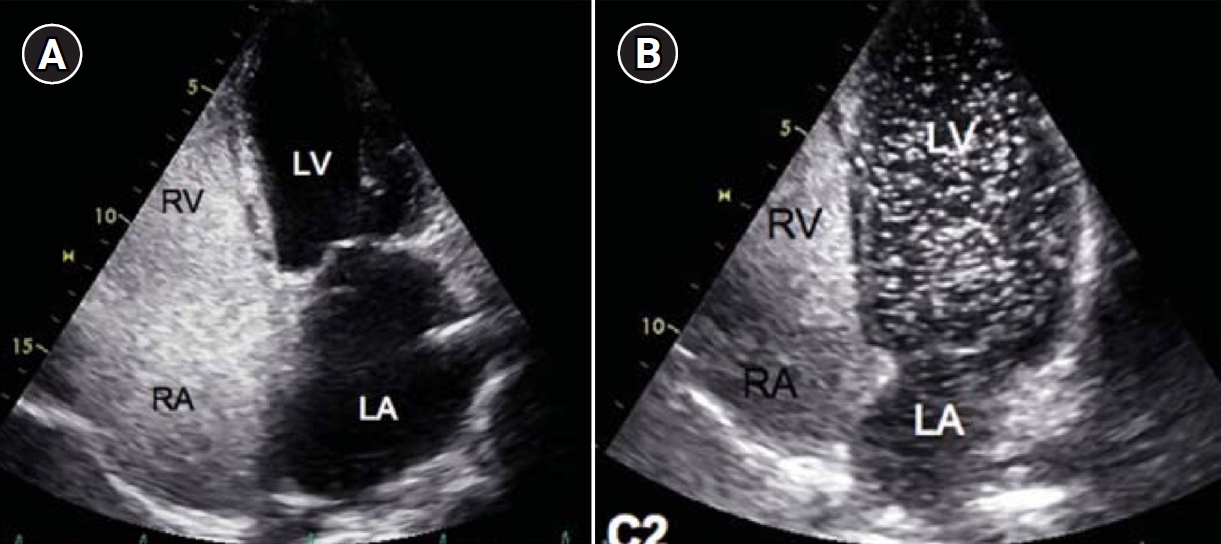

Fig. 1.

Agitated saline bubble echocardiography images. (A) After injection of agitated saline bubbles into a peripheral vein, echogenic bubbles are seen filling the right heart. Under normal conditions, the bubbles are completely filtered by the pulmonary capillary bed, and no bubbles appear in the left cardiac chambers. (B) After the appearance of bubbles in the right cardiac chambers, bubbles are subsequently observed in the left cardiac chambers after three cardiac cycles, indicating the presence of an extracardiac shunt (pulmonary arteriovenous malformation). RA, right atrium; RV, right ventricle; LA, left atrium; LV, left ventricle.

Fig. 1. Agitated saline bubble echocardiography images. (A) After injection of agitated saline bubbles into a peripheral vein, echogenic bubbles are seen filling the right heart. Under normal conditions, the bubbles are completely filtered by the pulmonary capillary bed, and no bubbles appear in the left cardiac chambers. (B) After the appearance of bubbles in the right cardiac chambers, bubbles are subsequently observed in the left cardiac chambers after three cardiac cycles, indicating the presence of an extracardiac shunt (pulmonary arteriovenous malformation). RA, right atrium; RV, right ventricle; LA, left atrium; LV, left ventricle.